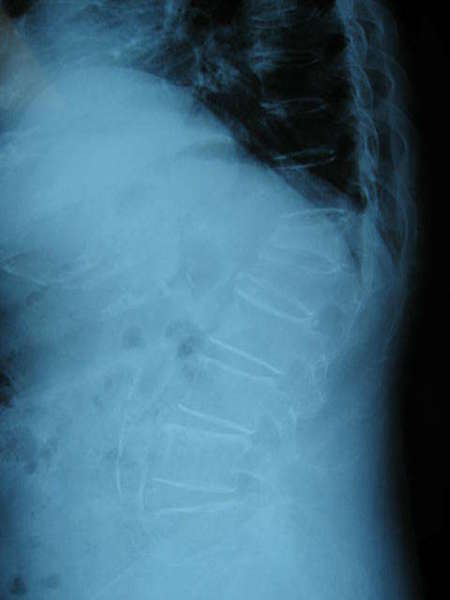

术前MRI(压脂)片----T12存在深出信号,L1信号正常